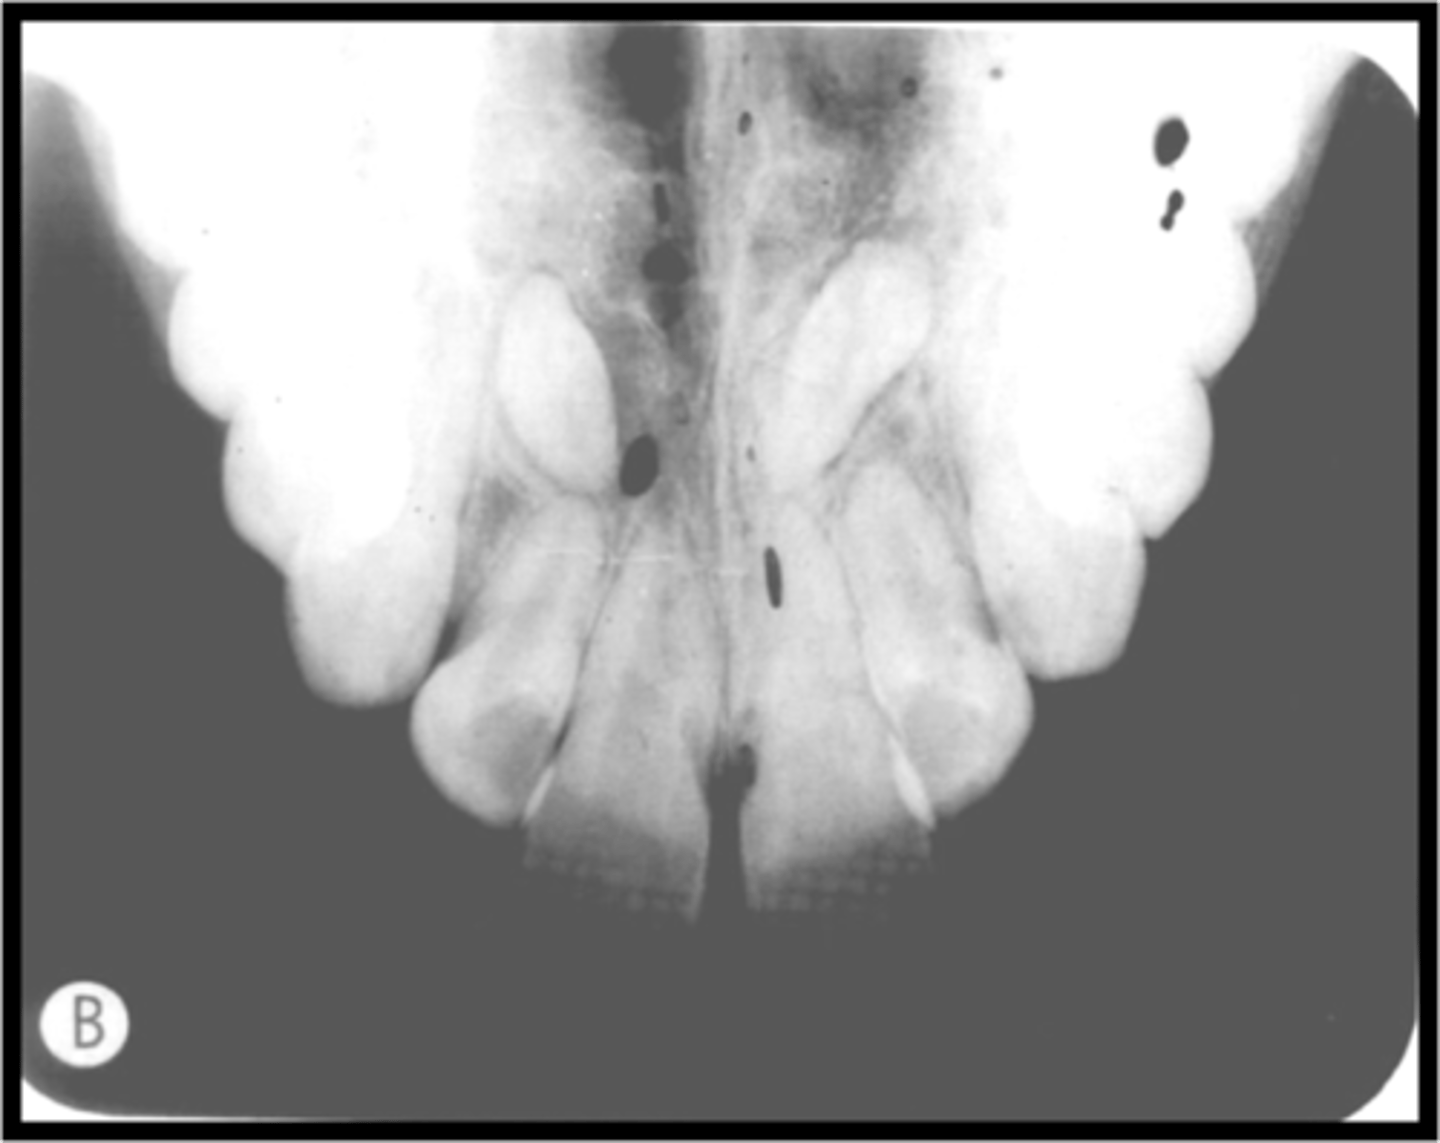

Phalangioma

Refers to the distal phalanx of the finger seen in the radiograph

-Image of the patient's finger is seen

-Error occurs when the finger-holding method is used with the bisecting technique and is not recommended

-To avoid make certain that the patient's finger used to stabilize the receptor is placed behind the receptor and not in front of it

Misc. errors-->Artifacts

-Glasses, Phalangioma, Dentures, lead apron or thyroid collar